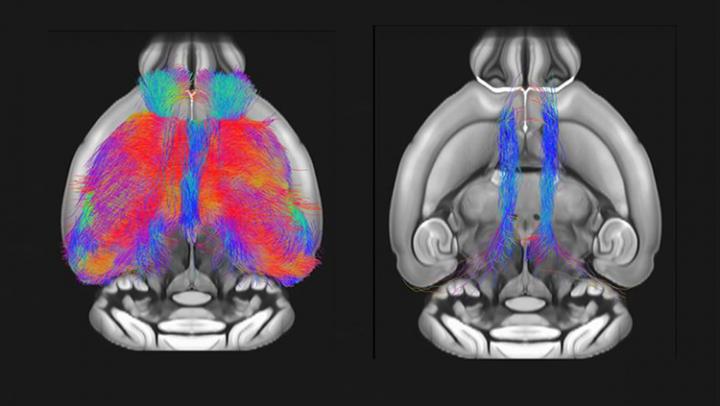

Mice lacking the gene Shank3 display structural and functional deficits in the prefrontal cortex, finds a study published in JNeurosci . The research advances our understanding of one of the most common genetic risk factors for autism spectrum disorders.

Using magnetic resonance imaging in adult male mice, Marco Pagani, Alessandro Gozzi and colleagues demonstrate reduced prefrontal cortex connectivity and gray matter volume in Shank3-deficient animals. The researchers report these brain differences are tightly linked to impaired social interaction with female mice. These findings establish a role of Shank3 in maintaining prefrontal cortex connectivity, which may increase autism risk when disrupted.